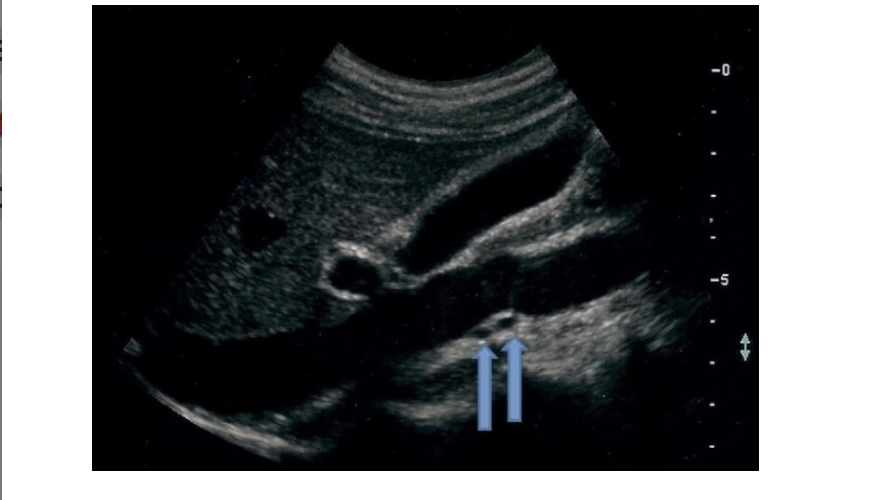

![<p>find the left renal vein</p><p>.</p><p>[left renal vein = between SMA + AO]</p>](https://knowt-user-attachments.s3.amazonaws.com/522e32e3-0c34-4507-81e5-c8f625b0171c.png)

find the left renal vein

.

[left renal vein = between SMA + AO]

left renal vein = between SMA + AO